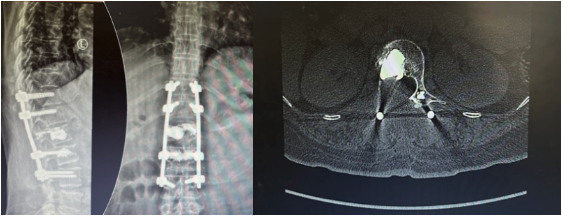

骨手术:

2024年3月19日在气管插管全麻下行腰椎转移瘤切除、椎管减压、骨水泥灌注、椎弓根钉内固定术,术后病理:骨组织脱钙后常规制:(腰椎椎体肿瘤)恶性肿瘤,结合病史及免疫组化符合乳腺癌转移,免疫组化结果:GATA3(+), ER(2+, 60%), PR(2+, 15%), C-erbB-2(2+), Syn(+), CgA(-), EMA(少许+), Ki-67(20%+)。 FISH阴性。(腰椎棘突)送检骨、软骨及骨髓组织,未见确切肿瘤累及。

2024年4月29日-2024年6月3日完成腰椎放疗25次。